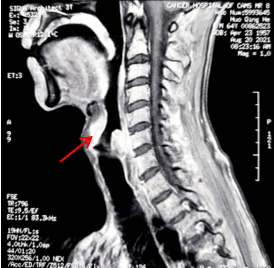

在急诊科完善了相关检查 , 上级医师刘宇此时查看了这位新来的患者 , 结合患者近期外院复查的影像发现患者下咽后壁及右侧不规则肿物 , 边界不清 , 上可达舌根部、口咽右侧壁 , 向下也已经累及会厌、右侧梨状窝、声带、室带、甲状软骨 (见红色箭头) 。 患者当前精神萎靡 , 床上稍活动后即气喘明显 , 入院查NT-proBNP水平明显升高 , 双肺CT可见肺纹理稀疏 , 多发肺大泡、小叶气肿 , 弥漫性磨玻璃小结节 , 散在斑片影 , 但是并未提示存在肺动脉高压、肺不张、气胸、大量的心包、胸腔积液等情况 。 刘宇分析病情:真假球麻痹、肺食管上纵隔肿瘤压迫喉返神经均可引发吞咽困难、声音嘶哑及饮水呛咳等症状 , 但该患者首先考虑下咽癌直接侵犯所致;中医症见神疲乏力、动则气喘、肌肤甲错 , 舌淡 , 脉沉细涩 , 属痰瘀互阻、肺肾气虚 。